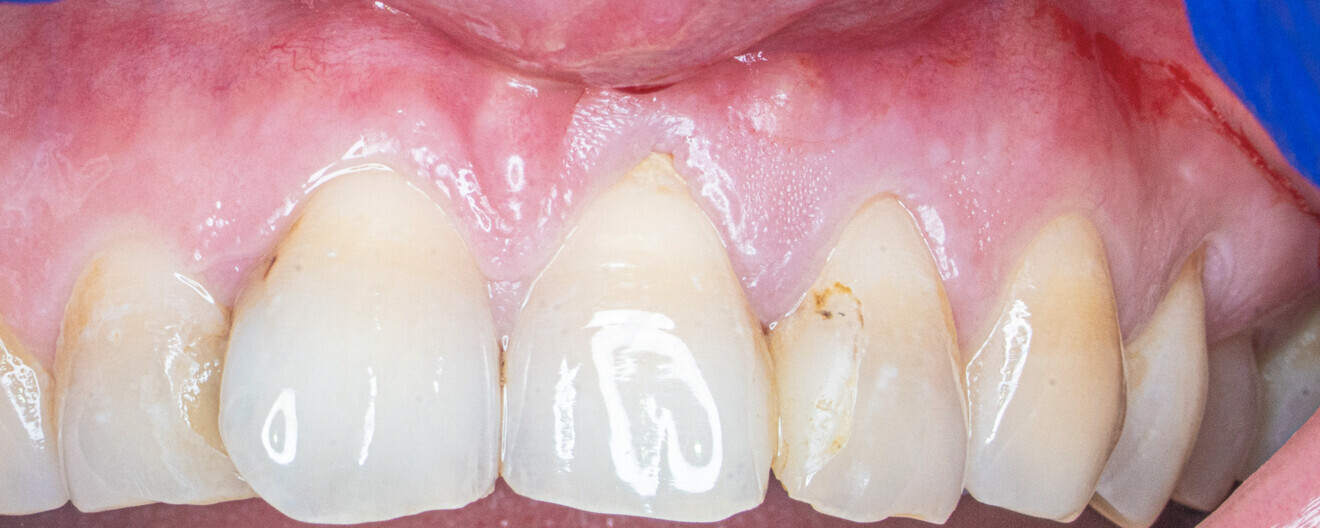

Fig. 5: Clinical situation after five months. No visible signs of inflammation.